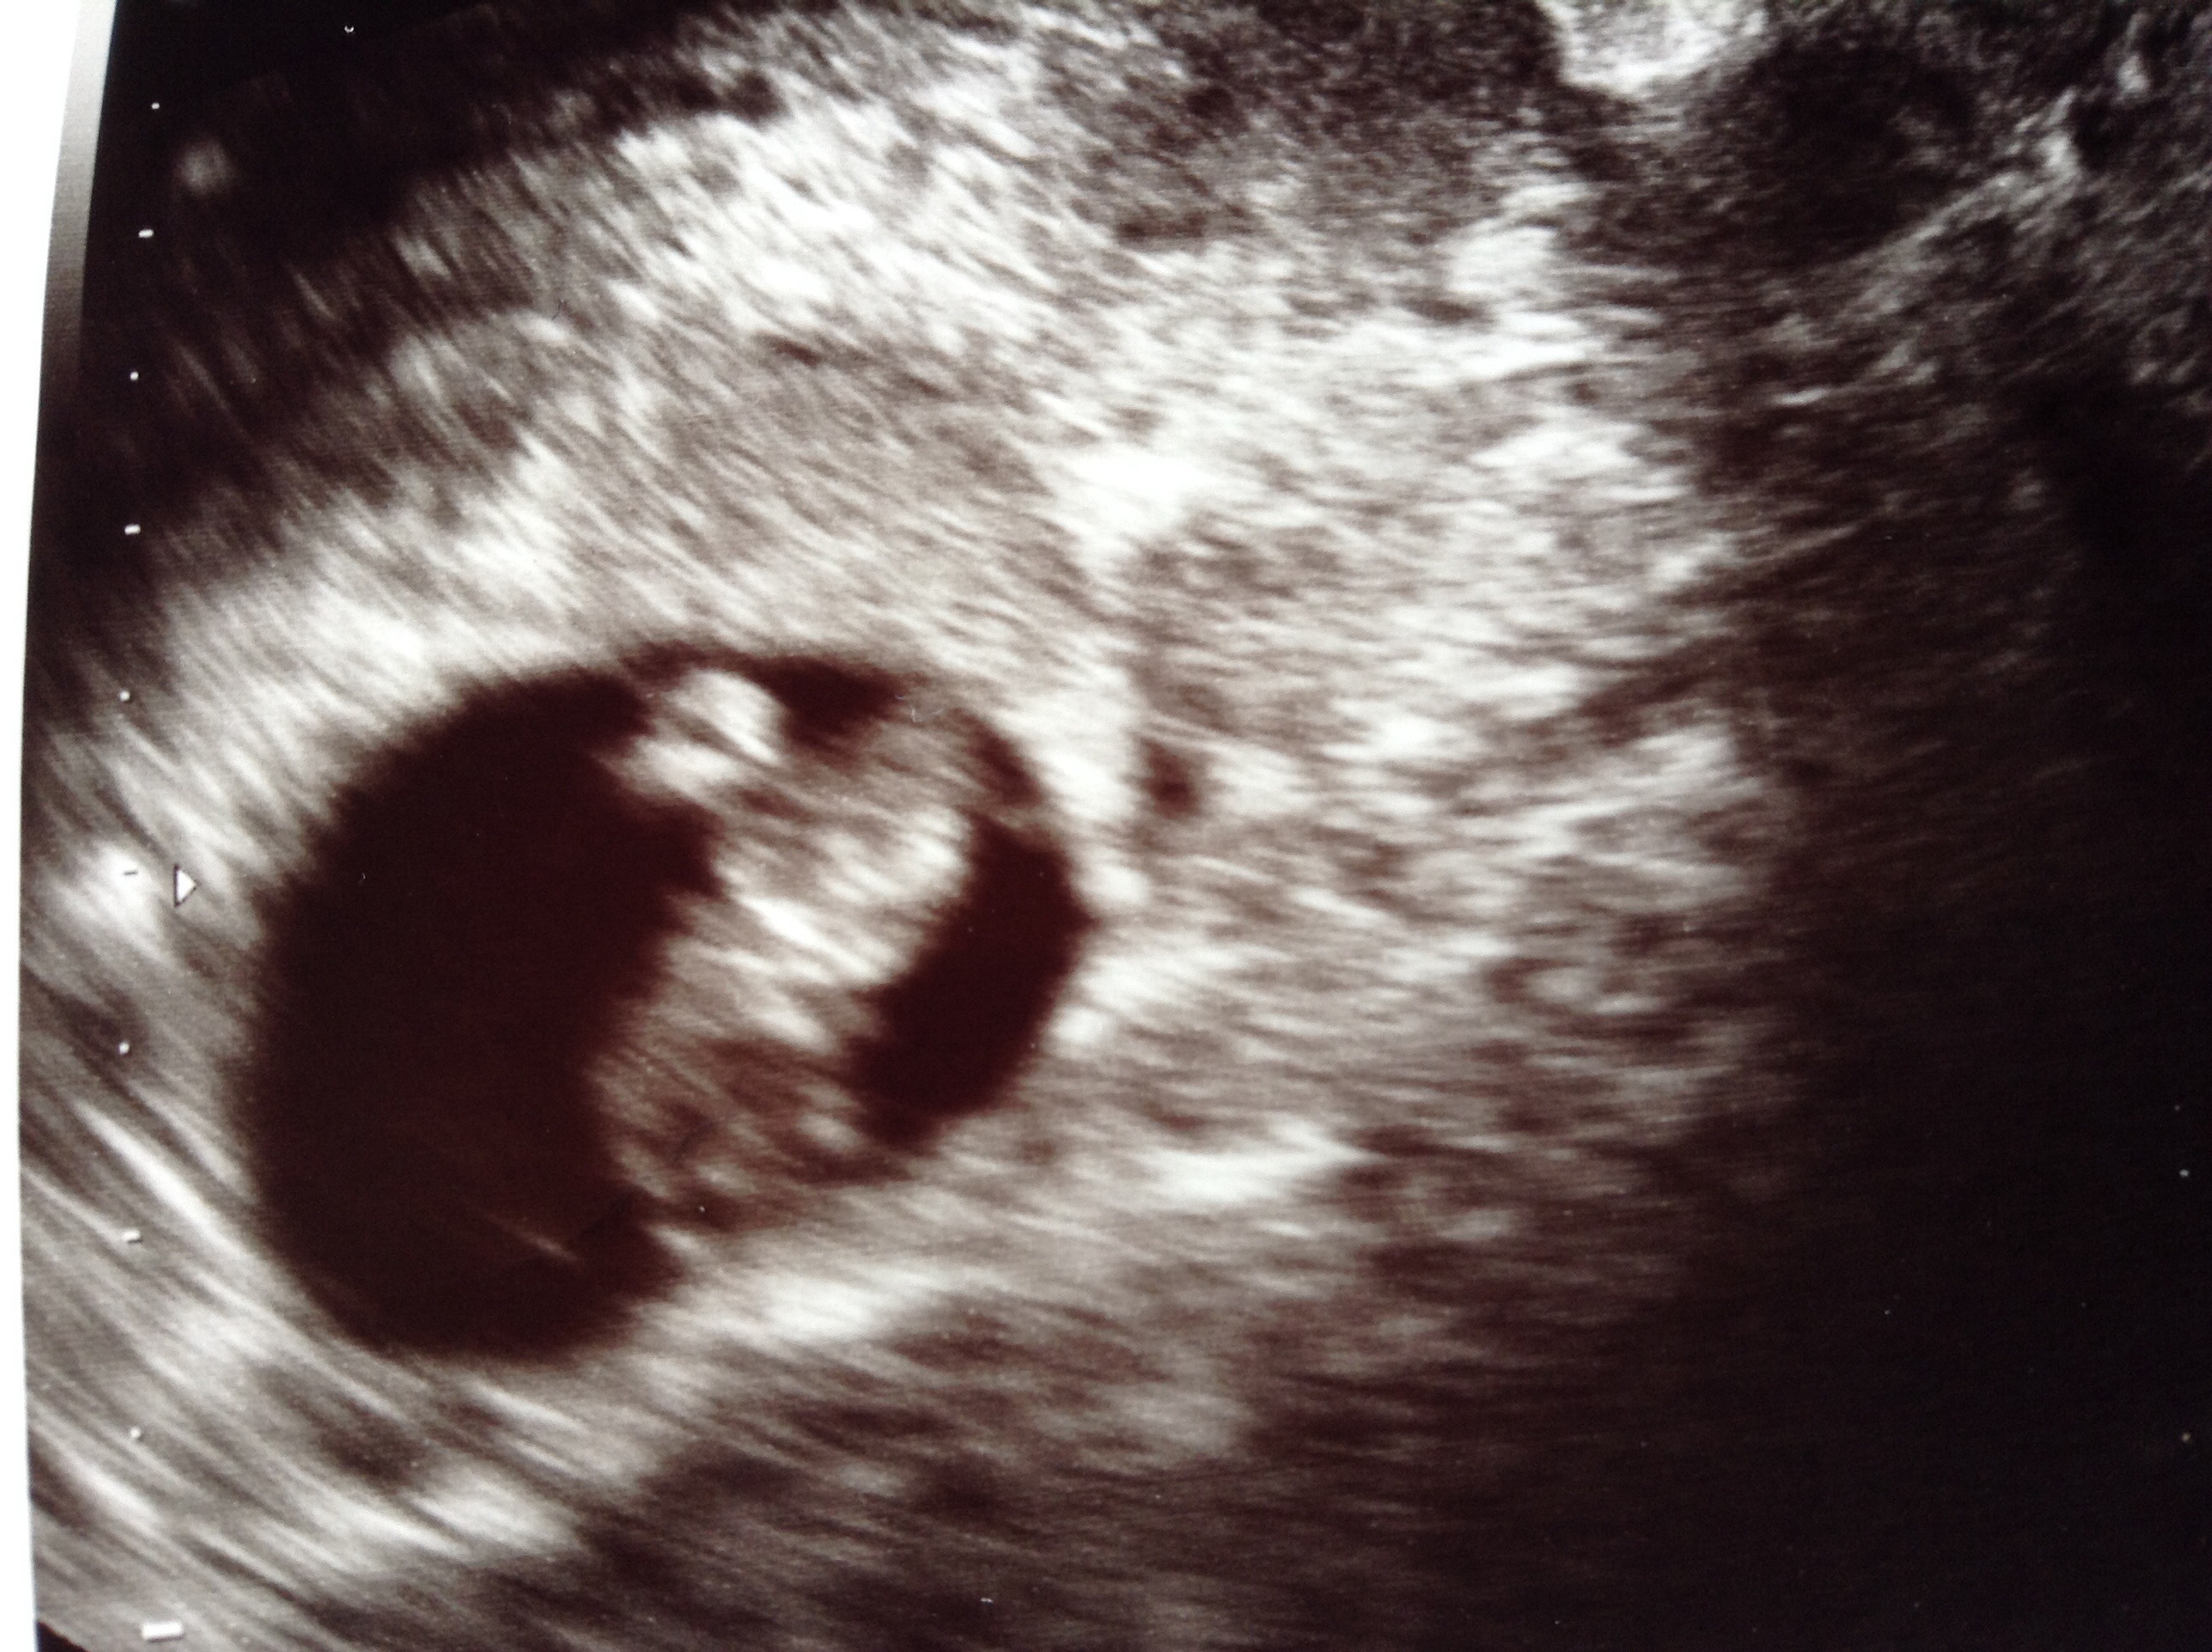

Meant to say this was an internal scan, I'm not sure if that makes a difference! X

This is a tricky one as not sure if scan is Sagittal or transverse view but if transverse would say boy but not a confident guess I'm afraid - I'm just going on fact that thicker white area seems to be to the right of baby which would mean baby is attached to right side which = boy.